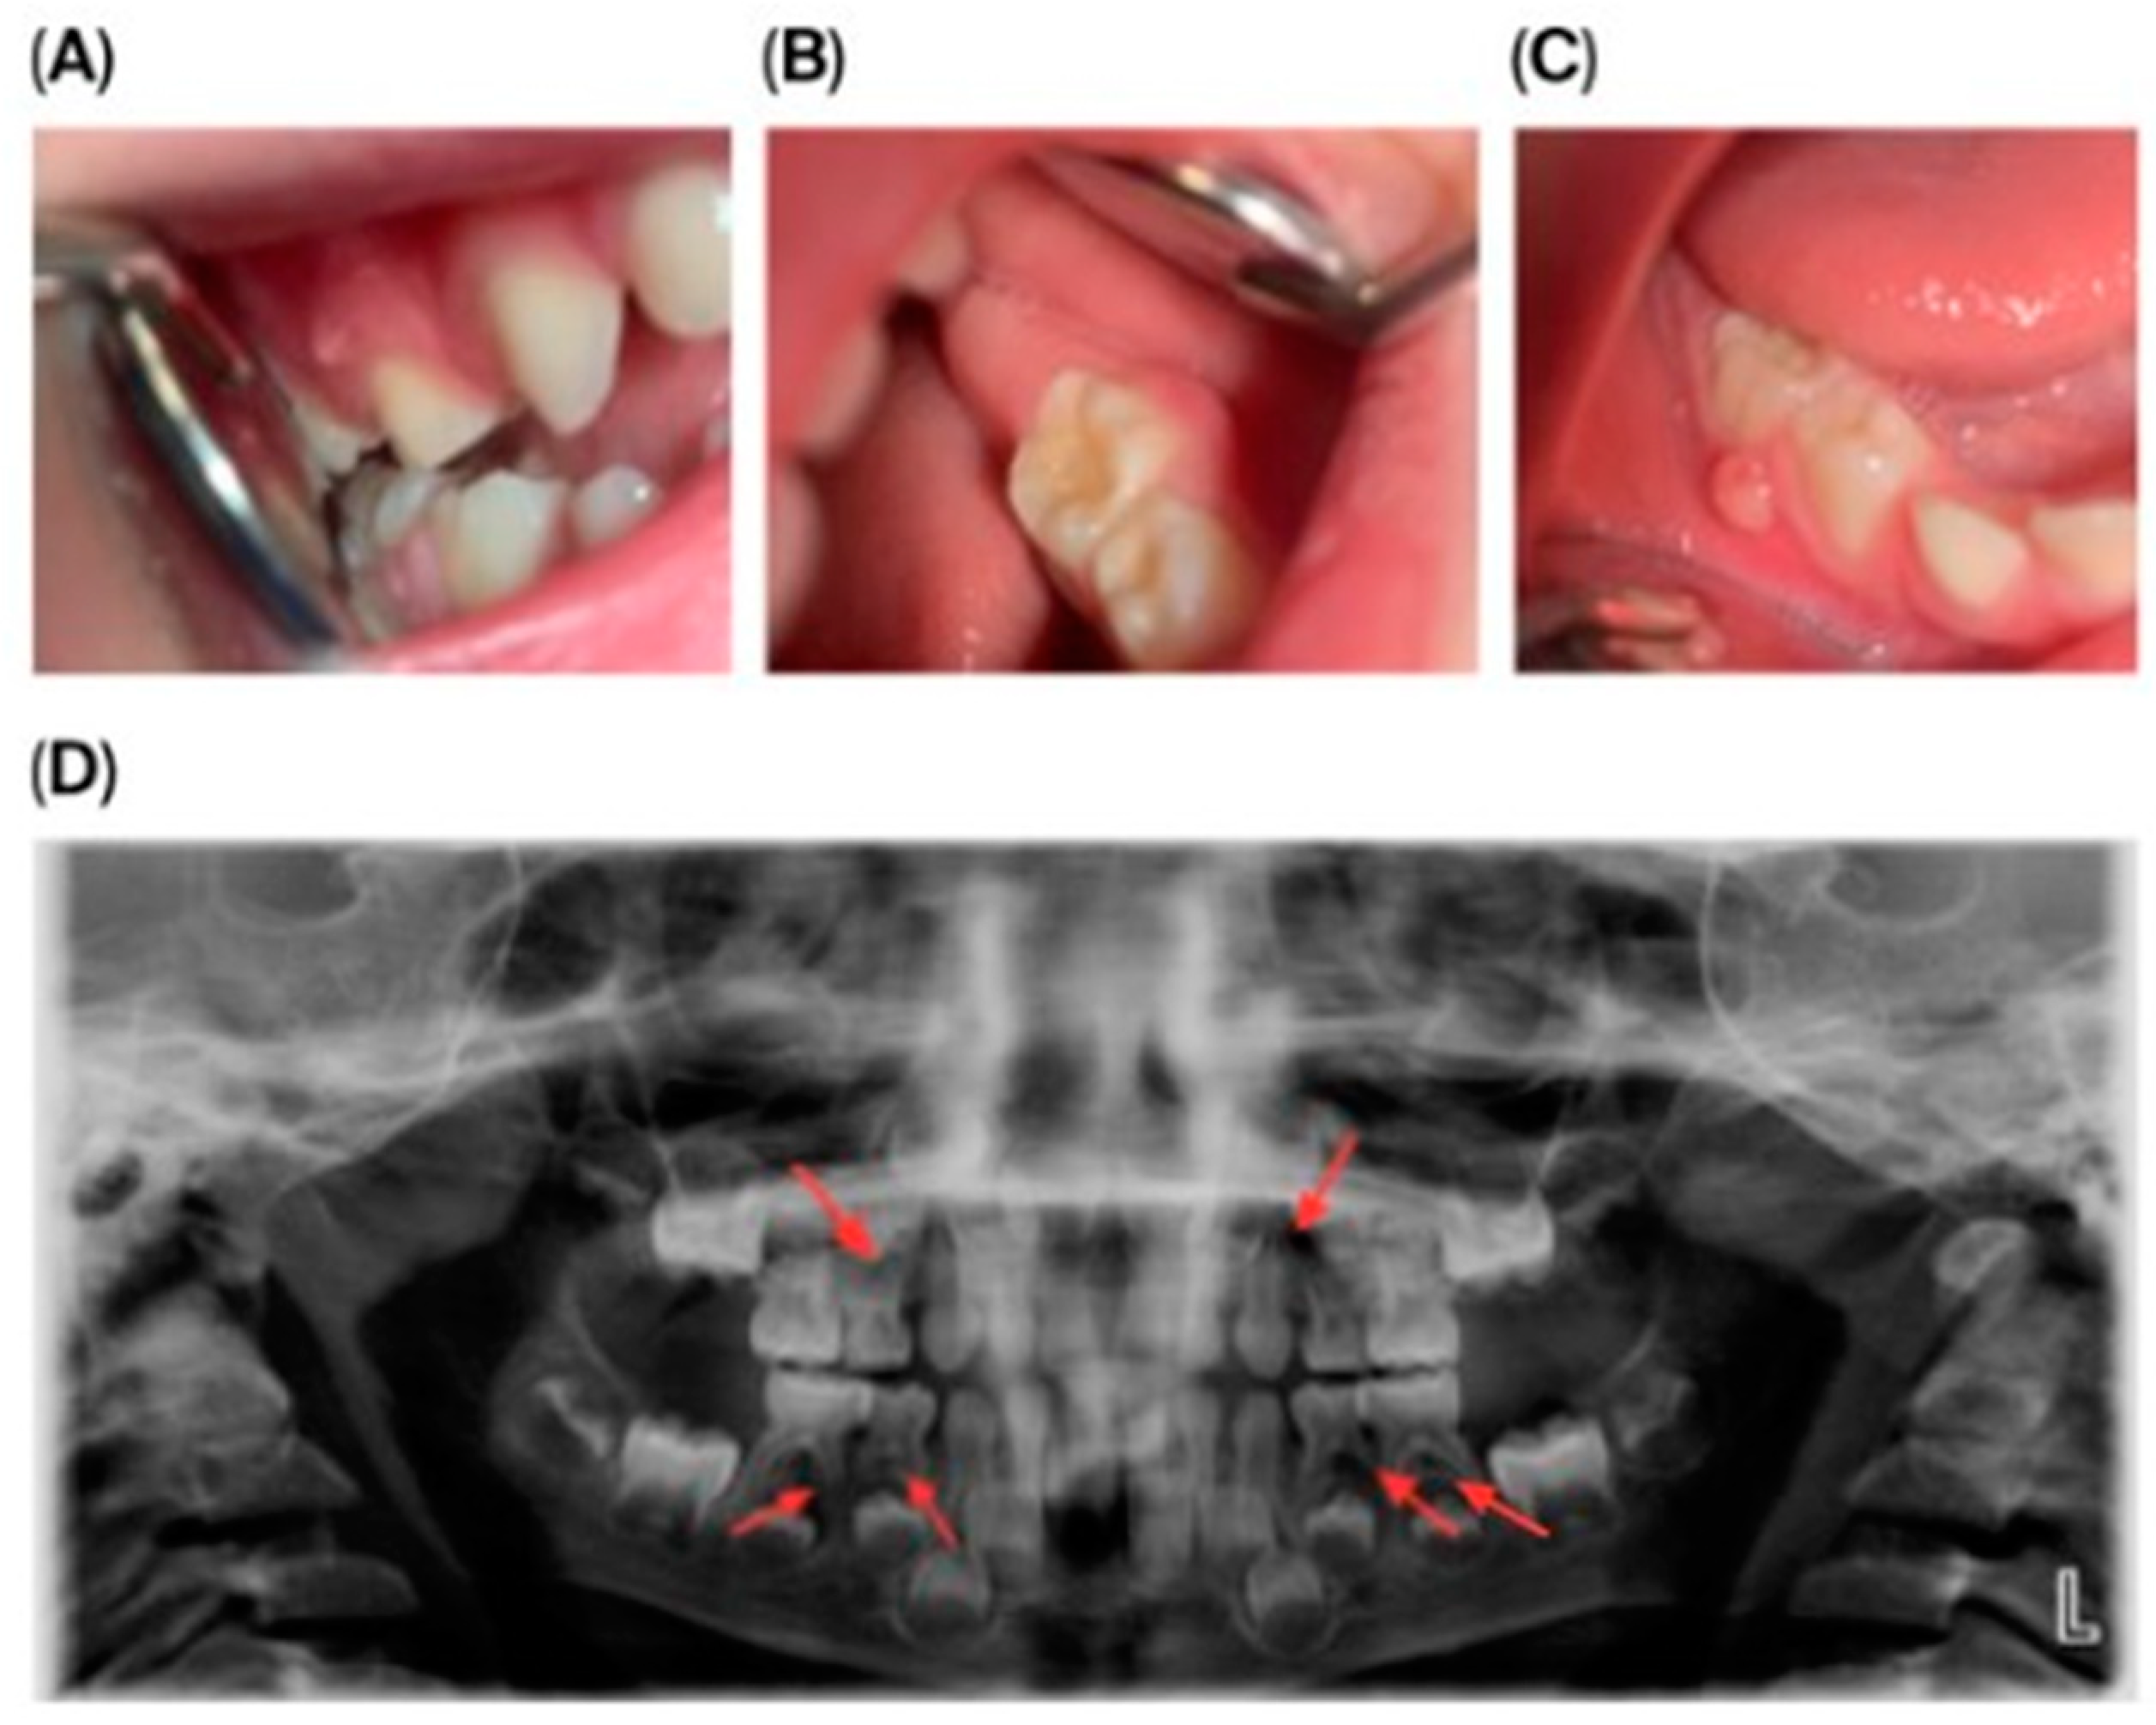

Dental Findings: Clinical and radiographic aspects: Intraoral examination revealed four fistulous openings on the buccal mucosa, located adjacent to the upper left first primary molar (tooth 64), upper right first primary molar (tooth 54), lower left second primary molar (tooth 75), and lower right second primary molar (tooth 85). The gingiva appeared normal, and there were no carious lesions or signs of trauma (Figure 1A–D).

Figure 1.

Intraoral and extraoral photographs and panoramic imaging of the patient showing multiple fistulas and dental pathology: (A) Buccal fistula in the upper right quadrant. (B) Buccal fistula in the lower left quadrant. (C) Buccal fistula in the lower right quadrant. (D) Panoramic radiograph (2024) showing extensive periapical radiolucency and root resorption in multiple primary molars (54, 64, 74, 75, 84, 85).

Panoramic radiography (Figure 1D) showed pronounced internal and external root resorption and extensive periapical radiolucency involving several primary molars (54, 64, 74, 75, 84, 85). The lesions measured approximately 2–4 mm, were diffuse, mainly affecting the furcation area and the medial roots, and displayed moderate, irregularly shaped root resorption. More advanced changes were observed in teeth 64, 74, and 85. The permanent tooth germs were intact, and no abnormalities of the eruption pattern or mineralization were noted at this stage.